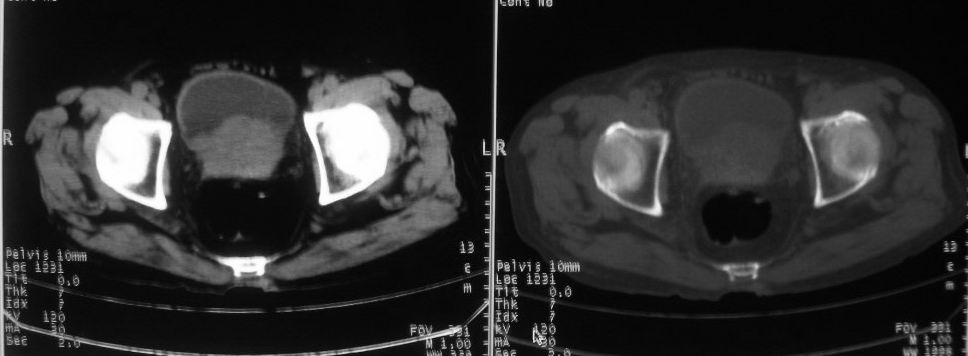

以下是引用zjzjr在2008-10-3 12:59:00的发言:[br]前列腺癌伴左髂骨\\腰椎转移可能性大.

以下是引用卜一在2008-10-3 13:40:00的发言:[br]前列腺癌!左髂骨\\腰椎转移?建议行全身骨扫描!

以下是引用深泽交通医院在2008-10-3 15:33:00的发言:[br]前列腺实性增大伴分叶状,与包膜间隙境界不清;椎体松质区间结节样密度影,考虑:前列腺癌,并椎体成骨性转移